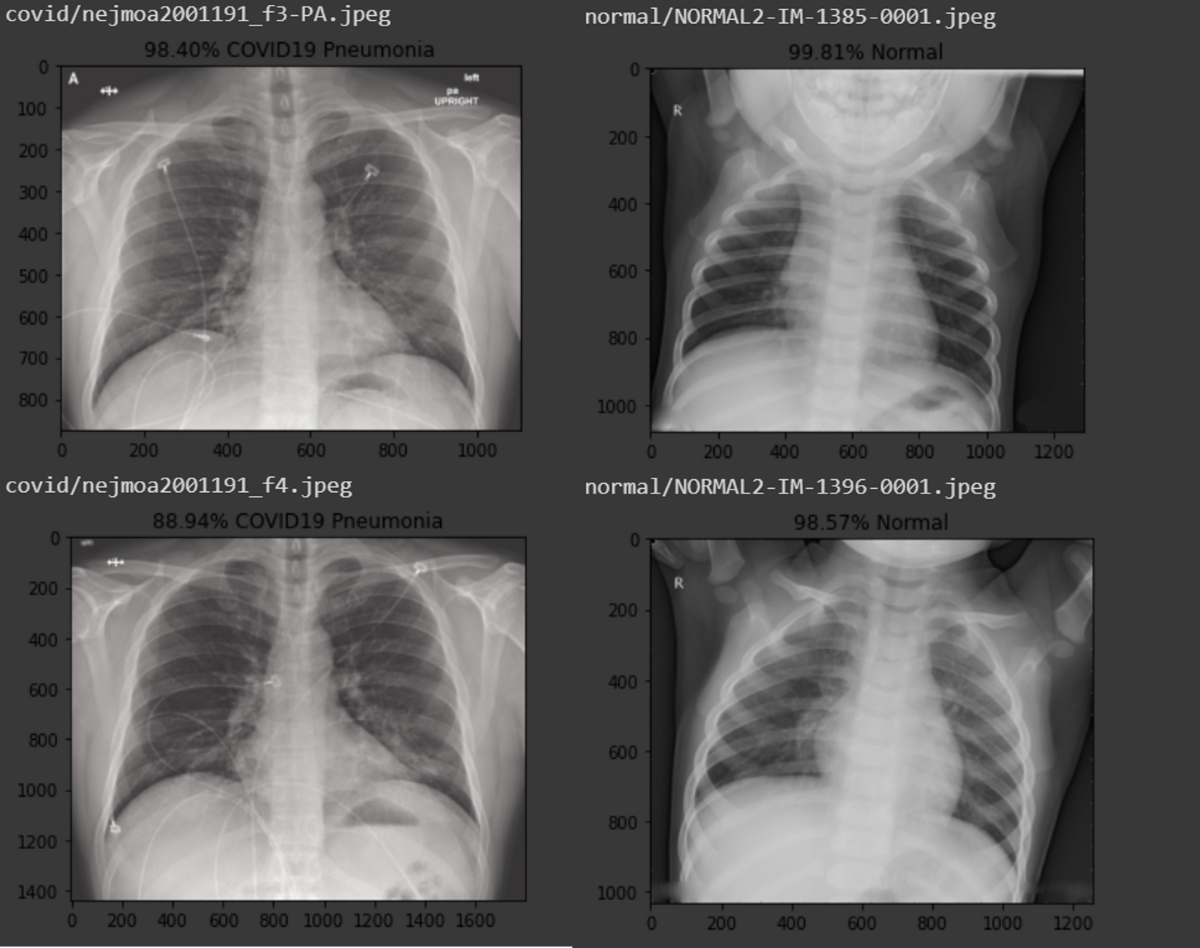

ყველაზე ხშირად კოვიდი პნევმონიისთვის (ფილტვების ანთება) დამახასიათებელი სიმპტომებით იწყება:

– ორმხრივი ინფილტრატები რენტგენსა თუ კომპიუტერულ ტომოგრაფიაზე.

#9. ვის სჭირდება გულმკერდის რენტგენოლოგიური ან კომპიუტერულ-ტომოგრაფიული კვლევა?

სამეცნიერო კვლევებმა აჩვენეს, თვით ასიმპტომატური პაციენტებიც რომ გამოვიკვლიოთ კომპიუტერული ტომოგრაფიით, აღმოვაჩენთ, რომ მათ ნახევარზე მეტს ფილტვების სხვადასხვა ხარისხის დაზიანება აღენიშნება. თუმცა, ეს რაიმე ტიპის სპეციფიკურ მკურნალობას არ საჭიროებს. მკურნალობის აუცილებლობას კლინიკური, ლაბორატორიული და კვლევებით მიღებული მონაცემების დაჯამების შედეგად განვსაზღვრავთ.

რადიოლოგიური კვლევა საწყის ეტაპზე მსუბუქად დაავადებულებს არ სჭირდებათ! თუ დაავადება მძიმდება და სუნთქვის უკმარისობით მიმდინარეობს, მხოლოდ მაშინ ხდება საჭირო განისაზღვროს დაზიანების ხარისხი. რადიოლოგიური კვლევა სრულიად უსაფრთხო არ არის; ის მცირედ დასხივებას იწვევს, ამიტომ არ შეიძლება მისი გამოყენება სპეციალური დანიშნულების გარეშე.